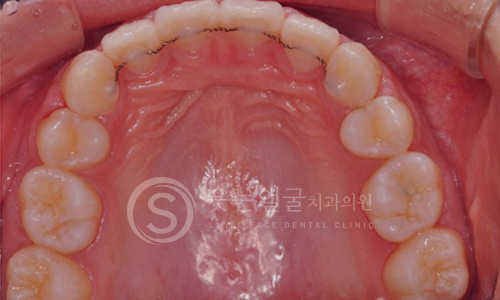

한눈에 보는

치아교정 전후사진